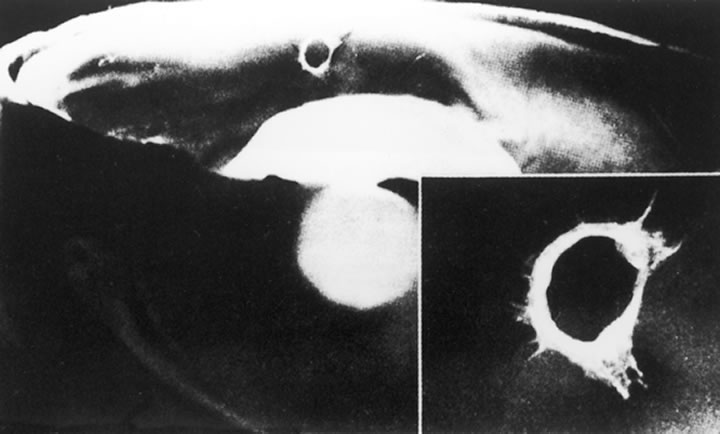

The nature of the adhesion between the vitreous cortex and the ILM is enigmatic. This adhesion is strongest at the optic nerve, the macula, the vitreous base, and retinal vessels. Foos6 demonstrated attachment plaques between Müller's cell cytoplasm and the ILM in the basal and equatorial retina (Fig. 2). Vitreous traction mediated by vitreous fibrils may contribute to these adhesions. These attachment plaques are not present posterior to the equator except where the ILM is thinned in the fovea. This anatomic variation in the fovea region may play a role in the pathogenesis of some of the vitreomacular disorders.